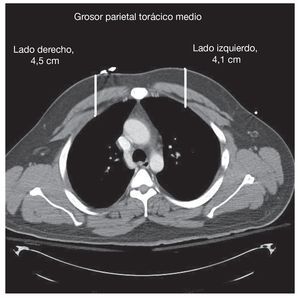

¿ La profundidad de la pared torácica media en el lado derecho fue de 4,5 ± 1,5 cm y en el lado izquierdo de 4,1 ± 1,4 cm.

En el grupo de pacientes incluidos en el estudio 82 (75%) fueron varones y 28 (25%) mujeres. En los grupos de estudio de enero, febrero y marzo hubo 25, 40 y 45 pacientes, respectivamente. La edad media fue de 43,5 años (rango, 18-85 años). El valor medio en la puntuación de gravedad del traumatismo fue de 17 (rango, 1-57). El grosor medio de la pared torácica en el lado derecho fue de 4,5 ± 1,5 cm y en el lado izquierdo de 4,1 ± 1,4 cm (fig. 2). El grosor medio de la pared torácica fue de 4,04 cm en los varones y de 5,14 en las mujeres. En conjunto, 55 de los 110 pacientes, correspondientes al 50% (intervalo de confianza [IC] del 95%, 40,7-59,3%), presentó un grosor de la pared torácica > 4,4 cm al menos en uno de los lados de su cuerpo.

FIGURA 2. Grosor parietal torácico promedio en los lados derecho e izquierdo.